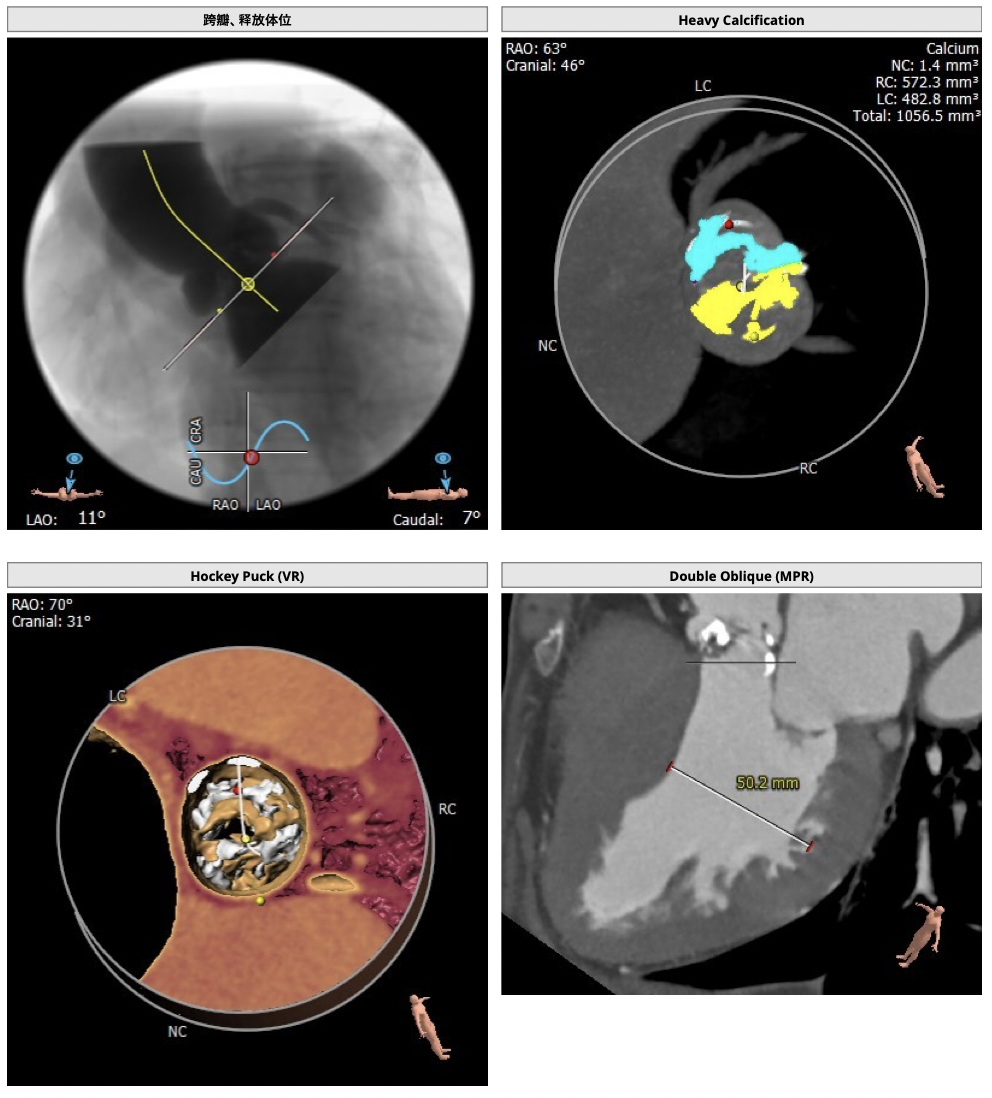

主动脉CT

图片

手术策略

CT分析:

*患者为TYPE1型二叶瓣,左右钙化融合,冠脉高度高,法式窦结构可,心脏角度约50°,左室大小可,心肌增厚,升主动脉未见明显增宽。主动脉弓部走形较平缓,右侧股动脉可作为主入路。

制定策略:

经分析研判,拟从右侧股动脉穿刺入路,使用23mm球囊预扩,选用L29号的VenusA-Valve瓣膜,采用VenusA-Plus可回收输送系统进一步确保手术安全,瓣膜释放后结合造影和超声情况,决定是否后扩。